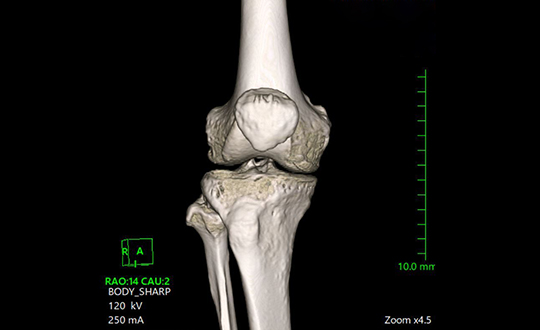

高速・高精細撮影により短時間で体内を詳しく撮影できるCT装置。80列検出器による高速撮影とAIDR 3D Enhanced技術で被ばくを低減し、安全性と精度の高い検査を行います。

関節疾患、スポーツ障害、骨折など、幅広い症例に対応可能で、患者様一人ひとりに合わせた治療方針を提案しています。術前検査から術後フォローまで一貫した対応が可能であり、地域の先生方との連携のもと、必要な症例に対し迅速かつ的確に対応します。